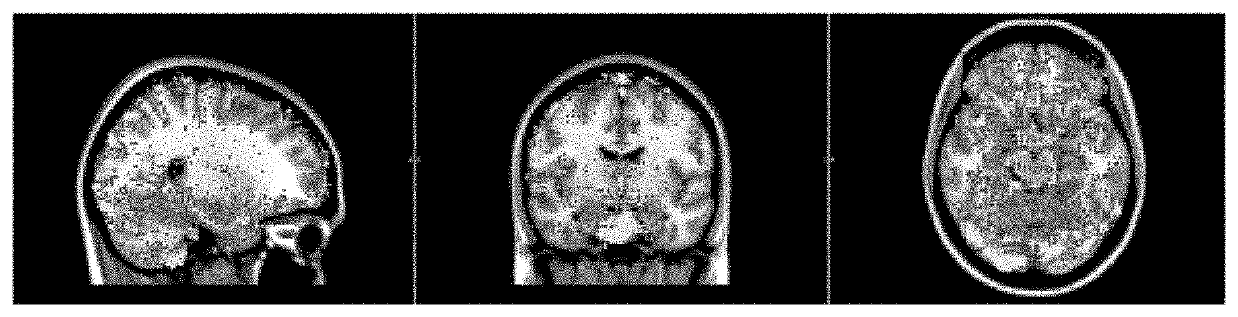

Systems and Methods for Imaging of Neurovascular-Coupling